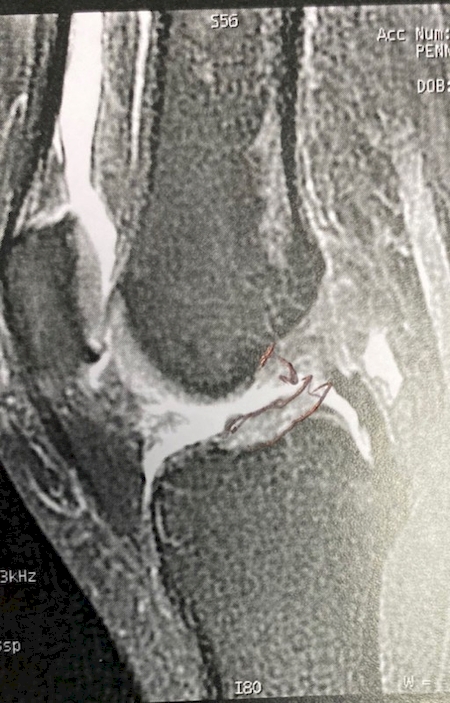

Réparation du ligament croisé antérieur : doit-on se faire opérer d'une rupture du ligament croisé du genou ? notre travail a l’IML marseille bouches du Rhône Réparation du ligament croisé antérieur : doit-on se faire opérer d'une rupture du ligament croisé du genou ? notre travail a l’IML marseille bouches du Rhône

Réparation du ligament croisé antérieur : doit-on se faire opérer d'une rupture du ligament croisé du genou ? notre travail a l’IML marseille bouches du Rhône

Chaque prise en charge doit être individualisée. La réparation du ligament croisé permettra demain de meilleur résultats cliniques chez des patients très selectionnées